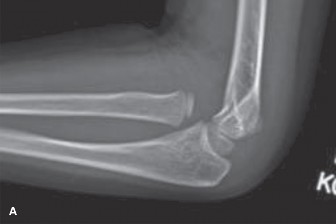

CASE 5 A 4-year-old girl fell from a playground structure, suffering the injury shown in the x-ray (Fig. 10–6A and B).

Figure 10–6 A